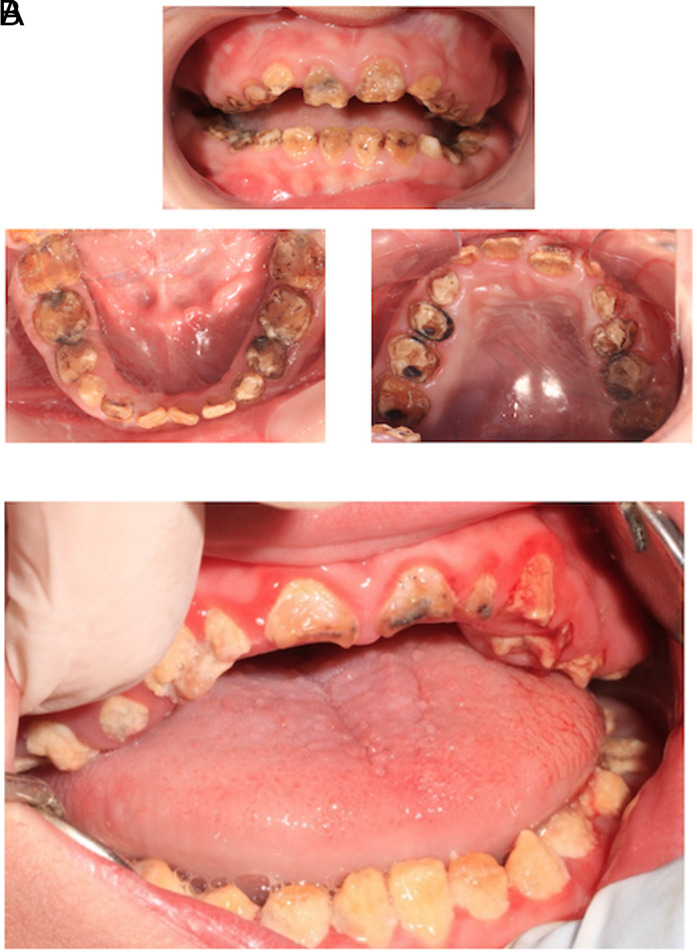

Kohlschütter-Tönz综合征(KTS) (OMIM#226750)是一种罕见的常染色体隐性遗传病,其特征为癫痫性脑病、发育迟缓和淀粉样变性不全。早期诊断和治疗至关重要,但症状的复杂性,特别是牙齿和神经损伤,构成了重大挑战。本报告的目的是描述2个兄弟姐妹的临床表现和他们的牙科管理,他们的牙科检查导致遗传转诊和随后诊断为KTS。牙科检查显示,两名兄弟姐妹的牙釉质缺陷与淀粉原性不完全性一致,包括黄棕色变色,软牙釉质和裂口。弟妹,一名9岁男孩,表现为早发性癫痫、智力残疾、痉挛和肾结石病史。哥哥是一名13岁的男孩,表现出更严重的神经发育迟缓、早发性癫痫和耐药性癫痫。基因检测证实了ROGDI基因的纯合缺失,从而在两个兄弟姐妹中诊断为KTS。弟弟妹妹在全身麻醉下接受了成功的恢复性治疗,而哥哥姐姐的口腔护理由于全身麻醉的禁忌症而被保守管理。这些病例强调了儿科牙医在早期识别罕见遗传疾病(如KTS)中的重要性,特别是当存在牙齿畸形(如无晶面发育不全)时。及时转诊进行遗传评估可以促进准确的诊断和适当的护理计划。此外,分享临床经验和治疗结果有助于更好地了解这种罕见综合征,并有助于指导未来的诊断和治疗策略。

Kohlschütter-Tönz syndrome (KTS) (OMIM#226750) is a rare autosomal recessive disorder characterized by epileptic encephalopathy, developmental delay, and amelogenesis imperfecta. Early diagnosis and management are crucial, but the complexity of symptoms, particularly dental and neurological impairments, poses significant challenges. The aim of this report is to describe the clinical findings of 2 siblings and their dental management, whose dental examination led to genetic referral and subsequent diagnosis of KTS. Dental examinations revealed enamel defects consistent with amelogenesis imperfecta, including yellow-brown discoloration, soft enamel, and diastemas in both siblings. The younger sibling, a 9-year-old boy, exhibited early-onset seizures, intellectual disability, spasticity, and a history of kidney stones. The older sibling, a 13-year-old boy, presented with more severe neurodevelopmental delay, early-onset seizures, and drug-resistant epilepsy. Genetic testing confirmed homozygous deletions in the ROGDI gene, leading to the diagnosis of KTS in both siblings. The younger sibling received successful restorative treatment under general anesthesia, while the older sibling's oral care was managed conservatively due to contraindications for general anesthesia. These cases underscore the importance of pediatric dentists in the early identification of rare genetic disorders such as KTS, especially when dental anomalies like amelogenesis imperfecta are present. Timely referral for genetic evaluation can facilitate accurate diagnosis and appropriate care planning. Moreover, sharing clinical experiences and treatment outcomes contributes to a better understanding of this rare syndrome and helps guide future diagnostic and therapeutic strategies.